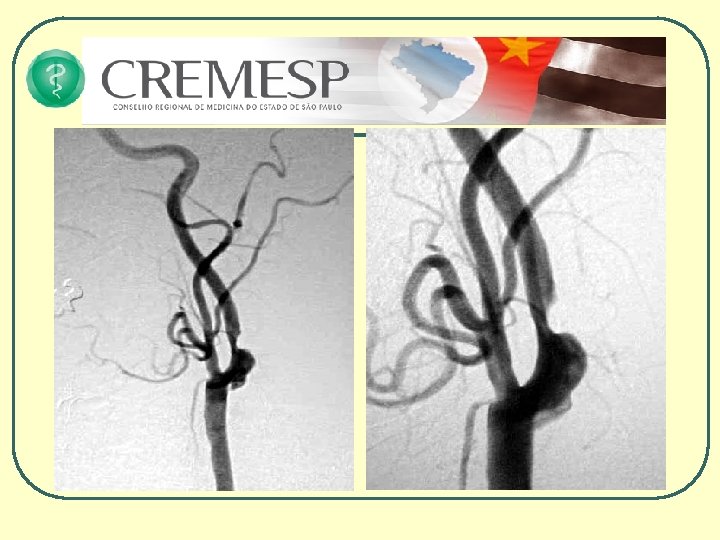

Vantagens da RM • Capacidade multiplanar • Melhor caracterização da lesão tecidual • Quanto ao tipo • Quanto à gravidade • Quanto à localização • Quanto à extensão • Melhor visualização do tronco cerebral • Angiografia • Difusão e Perfusão • Espectroscopia Programa de Educação Médica Continuada do CREMESP

Tratamento Medicamentoso • Trombólise com o uso intravenoso do ativador de plasminogênio tissular – t-PA dentro das primeiras 4 e ½ horas do início dos sintomas além da necessidade de seguir um protocolo rígido. (PORTARIA MS Nº 664, DE 12 DE ABRIL DE 2012 - Aprova o Protocolo Clínico e Diretrizes Terapêuticas Trombólise no AVCI Agudo. ) (www. portal. saude. gov. br) • Aspirina 200 a 500 mg na fase aguda do AVCI • Heparina e anticoagulação oral em situações especiais Programa de Educação Médica Continuada do CREMESP